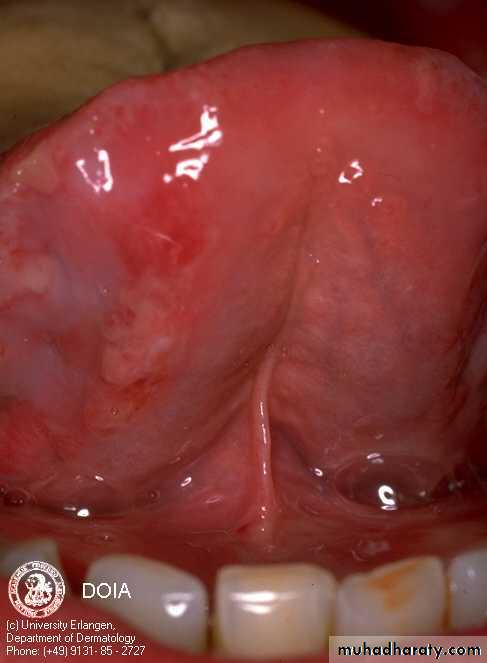

Mucous membranes of the mouth, pharynx and larynx may be involved and cause painful oral erosions, dysphagia and hoarseness of the voice respectively. Oral lesions (Painful erosions and ulcerations) are the presenting feature in about 50% of the patient and oral involvement occurs in almost all patients during the whole course of the disease.

Upper lip

Lower lipInner Cheek

Tongue

PV of the oral mucous membranes